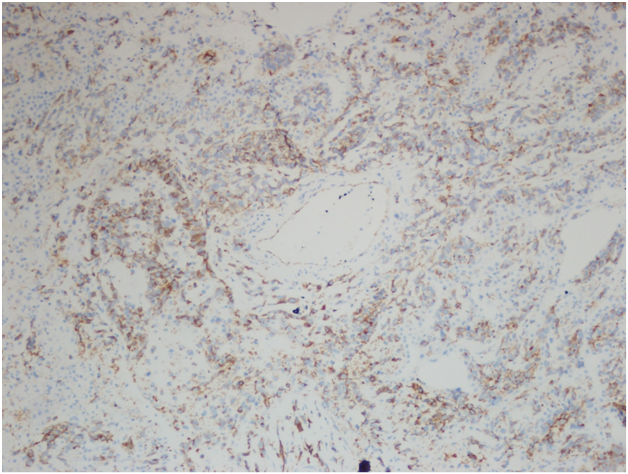

However, the wedge resection of the right lower lobe revealed angiosarcoma with lymphovascular invasion. This biopsy showed highly atypical and large malignant cells with increased mitoses (Figure 2A&2B). The immunohistochemical stains showed diffuse positivity for CD31, CD34, and vimentin (Figures 3A-3C). Stains for AE1/AE3 (Figure 3D), cam5.2, TTF-1, desmin, and OCT3/4 were negative. Along with the clinical history, a final diagnosis of angiosarcoma of the heart with metastases to the lungs was made.

The histology of this tumor has been described as irregular, anastomosing, vascular structures composed of endothelial-like cells, which can be either spindle-shaped or rounded and polygonal. Low grade lesions are composed of single- or multiple-layered vascular spaces while high grade lesions show sheets of poorly differentiated, pleomorphic cells.2 Immunohistochemical stain for CD31 is positive in 90% of PCAs and stain for FLI-1 in 100% of PCAs. Other commonly used positive stains include CD34, cytokeratins, vimentin and Factor VIII-related antigen,12 ranging from 35% to 74% positivity in PCAs described in the literature.